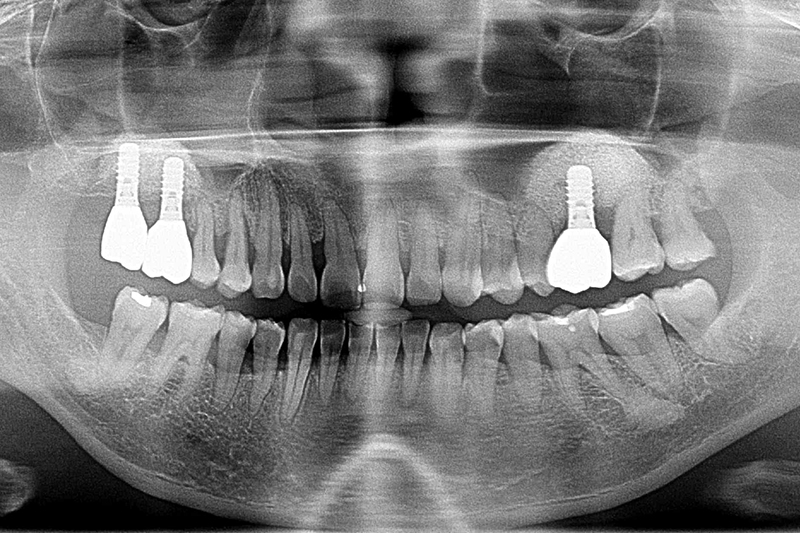

缺牙多顆-全口X光攝影

案例一

術前